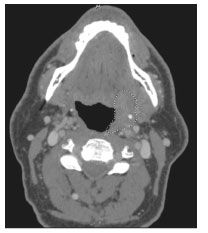

Figure 3. Neck CT scan showing a left tonsillar fossa mass (dashed lines) in a 57-year-old HIV-infected man with invasive squamous cell carcinoma.

Oral cancers appear to be more common in HIV-positive persons, and there may be an association between oral cancers, particularly tonsillar cancers, and HPV.95,96 We have recently diagnosed oral cancers in 2 HIV-positive persons at our centers (Figure 3) (S.K.C., T.G., J.R., unpublished data, 2007). Both patients had a preceding anal cancer. In 1 patient, metastases to the skin developed; all specimens from this patient were positive for HPV types 16 and 18 by in situ DNA hybridization.

Studies comparing cancer incidence in the HIV population with that in the general population have demonstrated a 2- to 3-fold increased incidence of oropharyngeal cancers associated with HIV infection.3-5 HIV-positive persons in whom oral cancers develop are generally younger than HIV-negative persons with oral cancers, and they have a poorer survival rate.97 Singh and colleagues97 compared 24 HIV-positive patients who had oral cancers with 515 HIV-negative oral cancer patients in the pre-HAART era. HIV-positive patients were younger at diagnosis, had more advanced tumor stage, and had a significantly poorer tumor-related survival rate (32% vs 59% at 2 years) than HIV-negative patients.

Recent publications provide evidence establishing a link between HPV infection and oral cancers, particularly tonsillar cancer.98,99 Syrjnen99 recently reviewed the published literature and found that 22% to 51% of oral cancers were positive for HPV DNA. The most prevalent serotypes by far were HPV types 16 and 18, which are also associated with cervical and anal cancers.53 In the general population, persons with HPV-positive oral cancers have a better prognosis than those with HPV-negative oral cancers.100 It is well established that HIV-positive persons are infected with more HPV subtypes than are HIV-negative persons,101 and they are 3 times as likely to have HPV type 16 or 18 isolated from oral mucosa.102